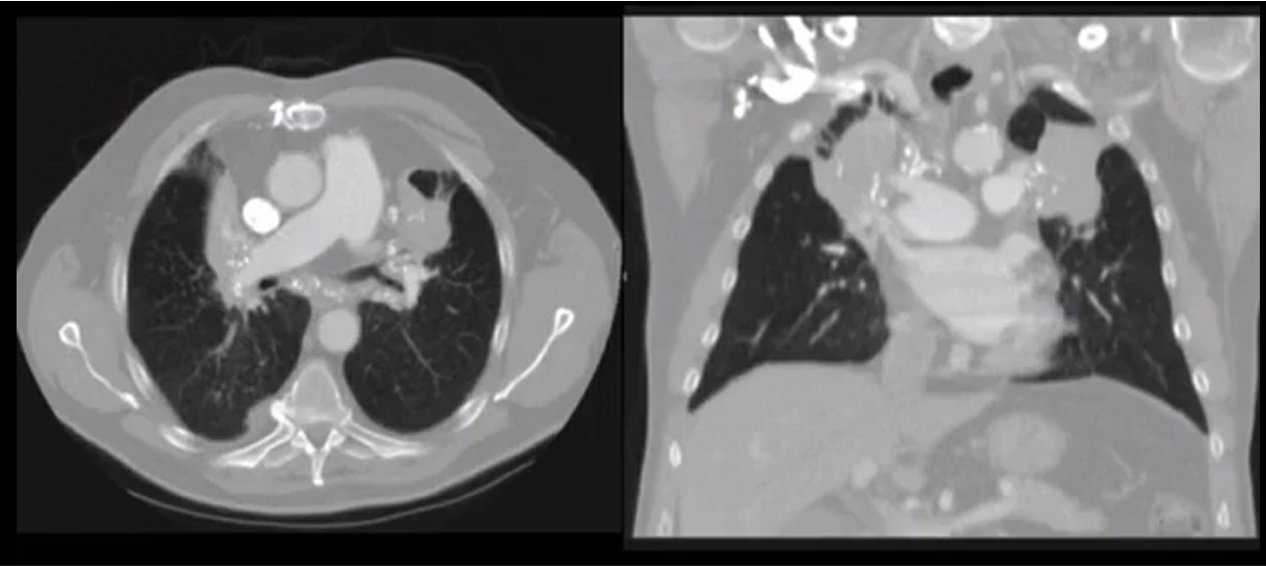

PLCH

smoker with cysts and nodules

pulmonary LCH